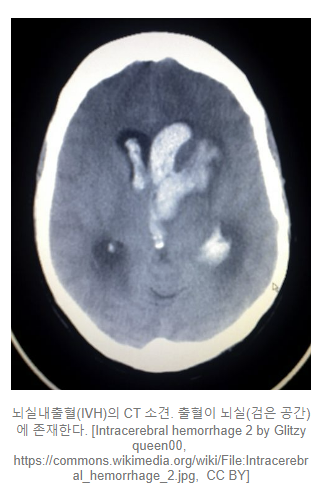

뇌실내출혈 (Intraventricular hemorrhage)

뇌실(cerebral ventricle)에 발생하는 뇌실내출혈은 뇌척수액이 흐르는 공간에 출혈이 동반되는 것을 이야기 합니다.

단독으로 발생하기도 하며, 지주막하출혈 혹은 뇌내출혈과 동반되어 발생하기도 합니다.

뇌압을 크게 상승시킬 우려가 있기 때문에 뇌실내출혈이 있을 경우, 치료의 핵심은 뇌압 및 혈압의 조절에 있습니다. 물론 양이 많을 경우에는 수술적 치료가 필요합니다.